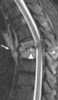

Osteomyelitis of spine

Osteomyelitis (OM) is an infection of bone. Symptoms may include pain in a specific bone with overlying redness, fever, and weakness. [Source: Wikipedia ]